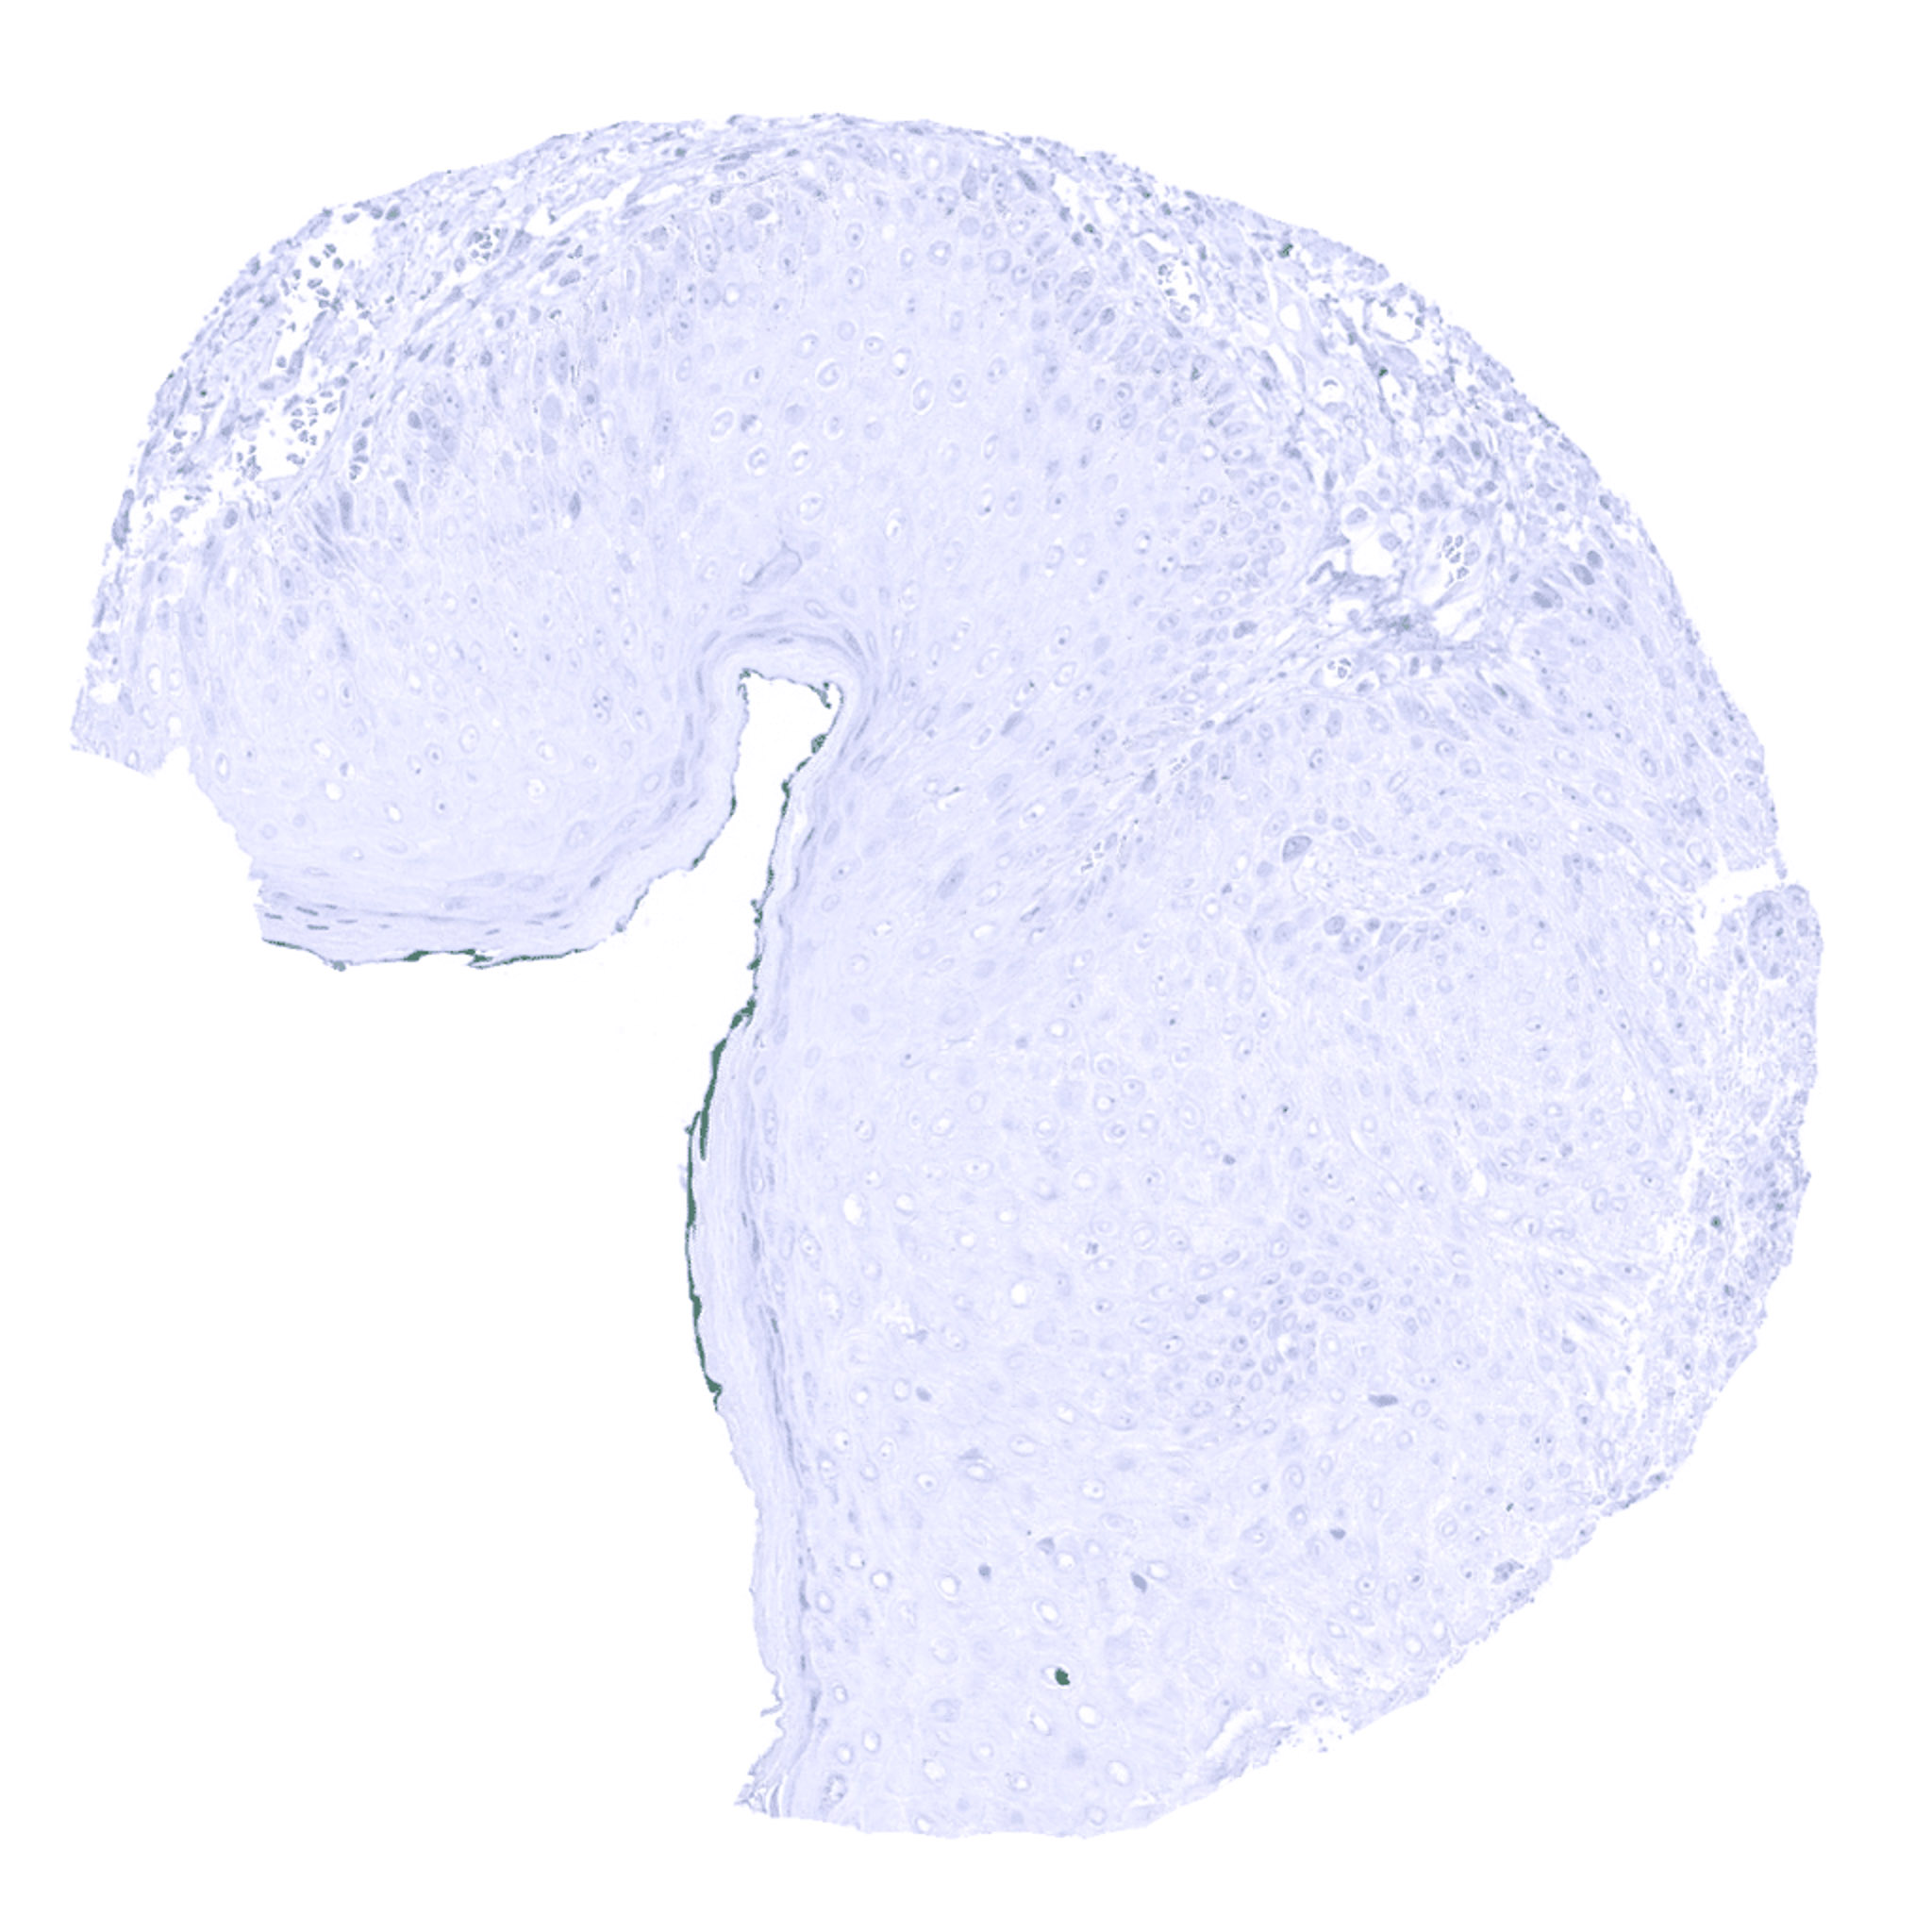

Parathyroid – Parathyroid gland showing intense cytoplasmic Parathyroid Hormone immunostaining of all glandular cells.

Parathyroid – Strong cytoplasmic Parathyroid Hormone immunostaining of all cells of a parathyroid gland.